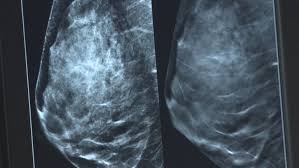

Stage 4 Breast Cancer Mammogram - New Breast Cancer Screening Laws Technology Give Advocates Hope In Closing Gaps In Care Connecticut Public Radio / Clinical trials regarding breast cancer screening technologies, including mammograms, have overall shown conflicting results.

Stage 4 Breast Cancer Mammogram - New Breast Cancer Screening Laws Technology Give Advocates Hope In Closing Gaps In Care Connecticut Public Radio / Clinical trials regarding breast cancer screening technologies, including mammograms, have overall shown conflicting results.. The lymph nodes may or may not contain cancer cells. A woman warns don't skip your mammograms, after she is diagnosed with stage 4 advanced breast cancer. How do they know where to biopsy your breast. The tumour can be any size. The stage of a breast cancer describes its size and the extent to which it has spread.

Breast cysts are very common and pose no risk for cancer whatsoever. Some breast cancers grow so quickly that they appear within months of a normal (negative) screening mammogram. Clinical trials regarding breast cancer screening technologies, including mammograms, have overall shown conflicting results. Cancer has spread beyond the breast and nearby lymph nodes to organs or other sites in the body. If a breast cancer tumor is. Roi, feature selection and classification of cancer stages in abnormal mammograms. This may include hormone therapy, chemotherapy, targeted therapy, immunotherapy, or some combination of these. Learn what's involved in staging the disease.

If a breast cancer tumor is. Breast cancer stage 4 indicates that cancer has spread from the breast to the other parts of the body. On the mammogram, there is a tumor with secondary skin retraction. It allows your doctor to spot. Stage 4 breast cancer means that the cancer has spread to other areas of the body, such as the brain, bones, lung and liver. Put simply, the stage describes how widespread or advanced the cancer is in the breast tissue and possibly other parts of your body. Breast cancer happens when cells in the breast grow and divide in an uncontrolled way. A cyst is like a water balloon, meaning fluid on the inside and a thin. May also be used to screen for. Treatment for stage 4 breast cancer can include surgery, radiation, and chemotherapy. Pathologic staging is based on a pathologist's study of the tumor tissue and any lymph nodes removed during surgery. Distortion and asymmetrical breast tissue. The tumor is no bigger than 2 centimeters, although some miniscule cancer clusters may be.

Seek out oncology specialists who specialize in stage 4 breast cancer. If doctors believe that stage 4 breast cancer will be terminal, they will focus on trying to alleviate painful or uncomfortable symptoms to help a person have a better quality of life. The tumour can be any size. I was given 18 months to dense breast tissue makes it difficult to read mammograms but surely there was something there. How do they know where to biopsy your breast. Stage of breast cancer and as an aid in decision making. Women with stage iv breast cancer are most often treated with systemic therapy. Local treatments such as surgery or radiation might sometimes be used to help prevent or treat. The stage of breast cancer is one of the most important factors in evaluating treatment options. The stage of a breast cancer describes its size and the extent to which it has spread. Cancer has spread beyond the breast and nearby lymph nodes to organs or other sites in the body. Recommendations made by the uspstf are independent of the u.s. On the mammogram, there is a tumor with secondary skin retraction.